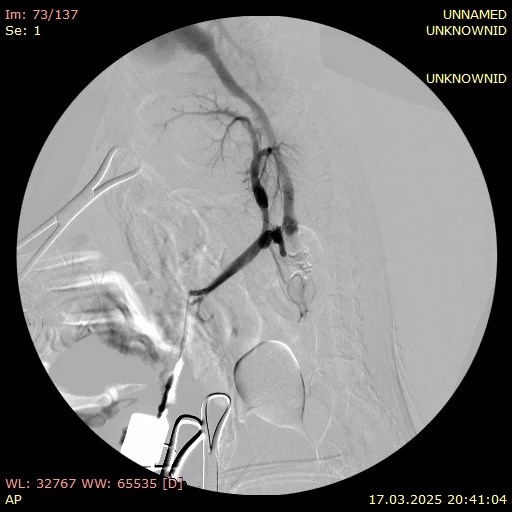

В этот же день пациенту были проведены хирургическое лечение (лапаротомия с аспирацией 800 мл прозрачной жидкости) и портография. Органы брюшной полости расположены анатомически правильно, висцеральный жир умеренно выражен. Сосуды брюшной полости расширены, селезенка умеренно увеличена. Печень значительно уменьшена в размерах, имеет желто-коричневый цвет и сглаженную зернистость. В паренхиме выявлены множественные включения светлого цвета. Желчный пузырь слабо наполнен, мягкий при пальпации. Желудок и кишечник без особенностей, перистальтика выражена хорошо. Измерение давления в портальной вене показало 20 мм вод. ст.Портография выявила множественные шунты: между портальной веной и каудальной полой веной, а также два спленоазигональных шунта (фото 5).